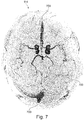

• Fig. 7 shows a further view of image 114.

• Fig. 7 there are three regions which are surrounded by dashed lines and marked 700. These are marked regions 700.

• the marked regions show mismatches in the analysis of the images and when plotted may also be plotted and colored for emphasis. They may indicate pathological alterations of the vessels and/or technical issues during acquisition.

• the visualization of venous vessels appears due to technical issues perhaps for insufficient saturation during acquisition of data.

• the attention of the radiologist can be pinpointed to critical areas and may assist in overall diagnostic process or the adjustment of the acquisition of the images.

• Mismatches in the analysis of the images may be color-coded and can indicate pathological alterations of the vessels and technical issues.

• the marked regions 700 indicate visualizations of venous vessels appeared due to technical issues (insufficient saturation). By this, the attention of the radiologist can be pinpointed to critical areas, supporting the overall diagnostic process.

• Fig. 8 shows an example of a composite angiographic image 128 that was constructed using the static angiographic image 114 and the time series of angiographic images 116' from Figs. 5 and 6 .

• the composite angiographic image is a mapped TOF angiographic image with the temporal information from ASL presented as time of arrival map. Since ASL images only present arterial vessels, the presented image analysis can avoid visualization of venous vessels which may appear in QF images due to technical issues such as insufficient saturation as was indicated in Fig. 7 . It is noted that the artifacts illustrated in Fig. 7 are not present in Fig. 8.

• Fig. 7 shows an example of a composite angiographic image 128 that was constructed using the static angiographic image 114 and the time series of angiographic images 116' from Figs. 5 and 6 .

• the composite angiographic image is a mapped TOF angiographic image with the temporal information from ASL presented as time of arrival map. Since A

• FIG. 8 shows a mapped TOF image with the temporal information from ASL presented as a time-of-arrival map. Since ASL images only present arterial vessels, the presented image analysis can avoid the visualization of venous vessels which may appear in TOF images due to technical issues (insufficient saturation). This can be indicated as in Fig. 7 .